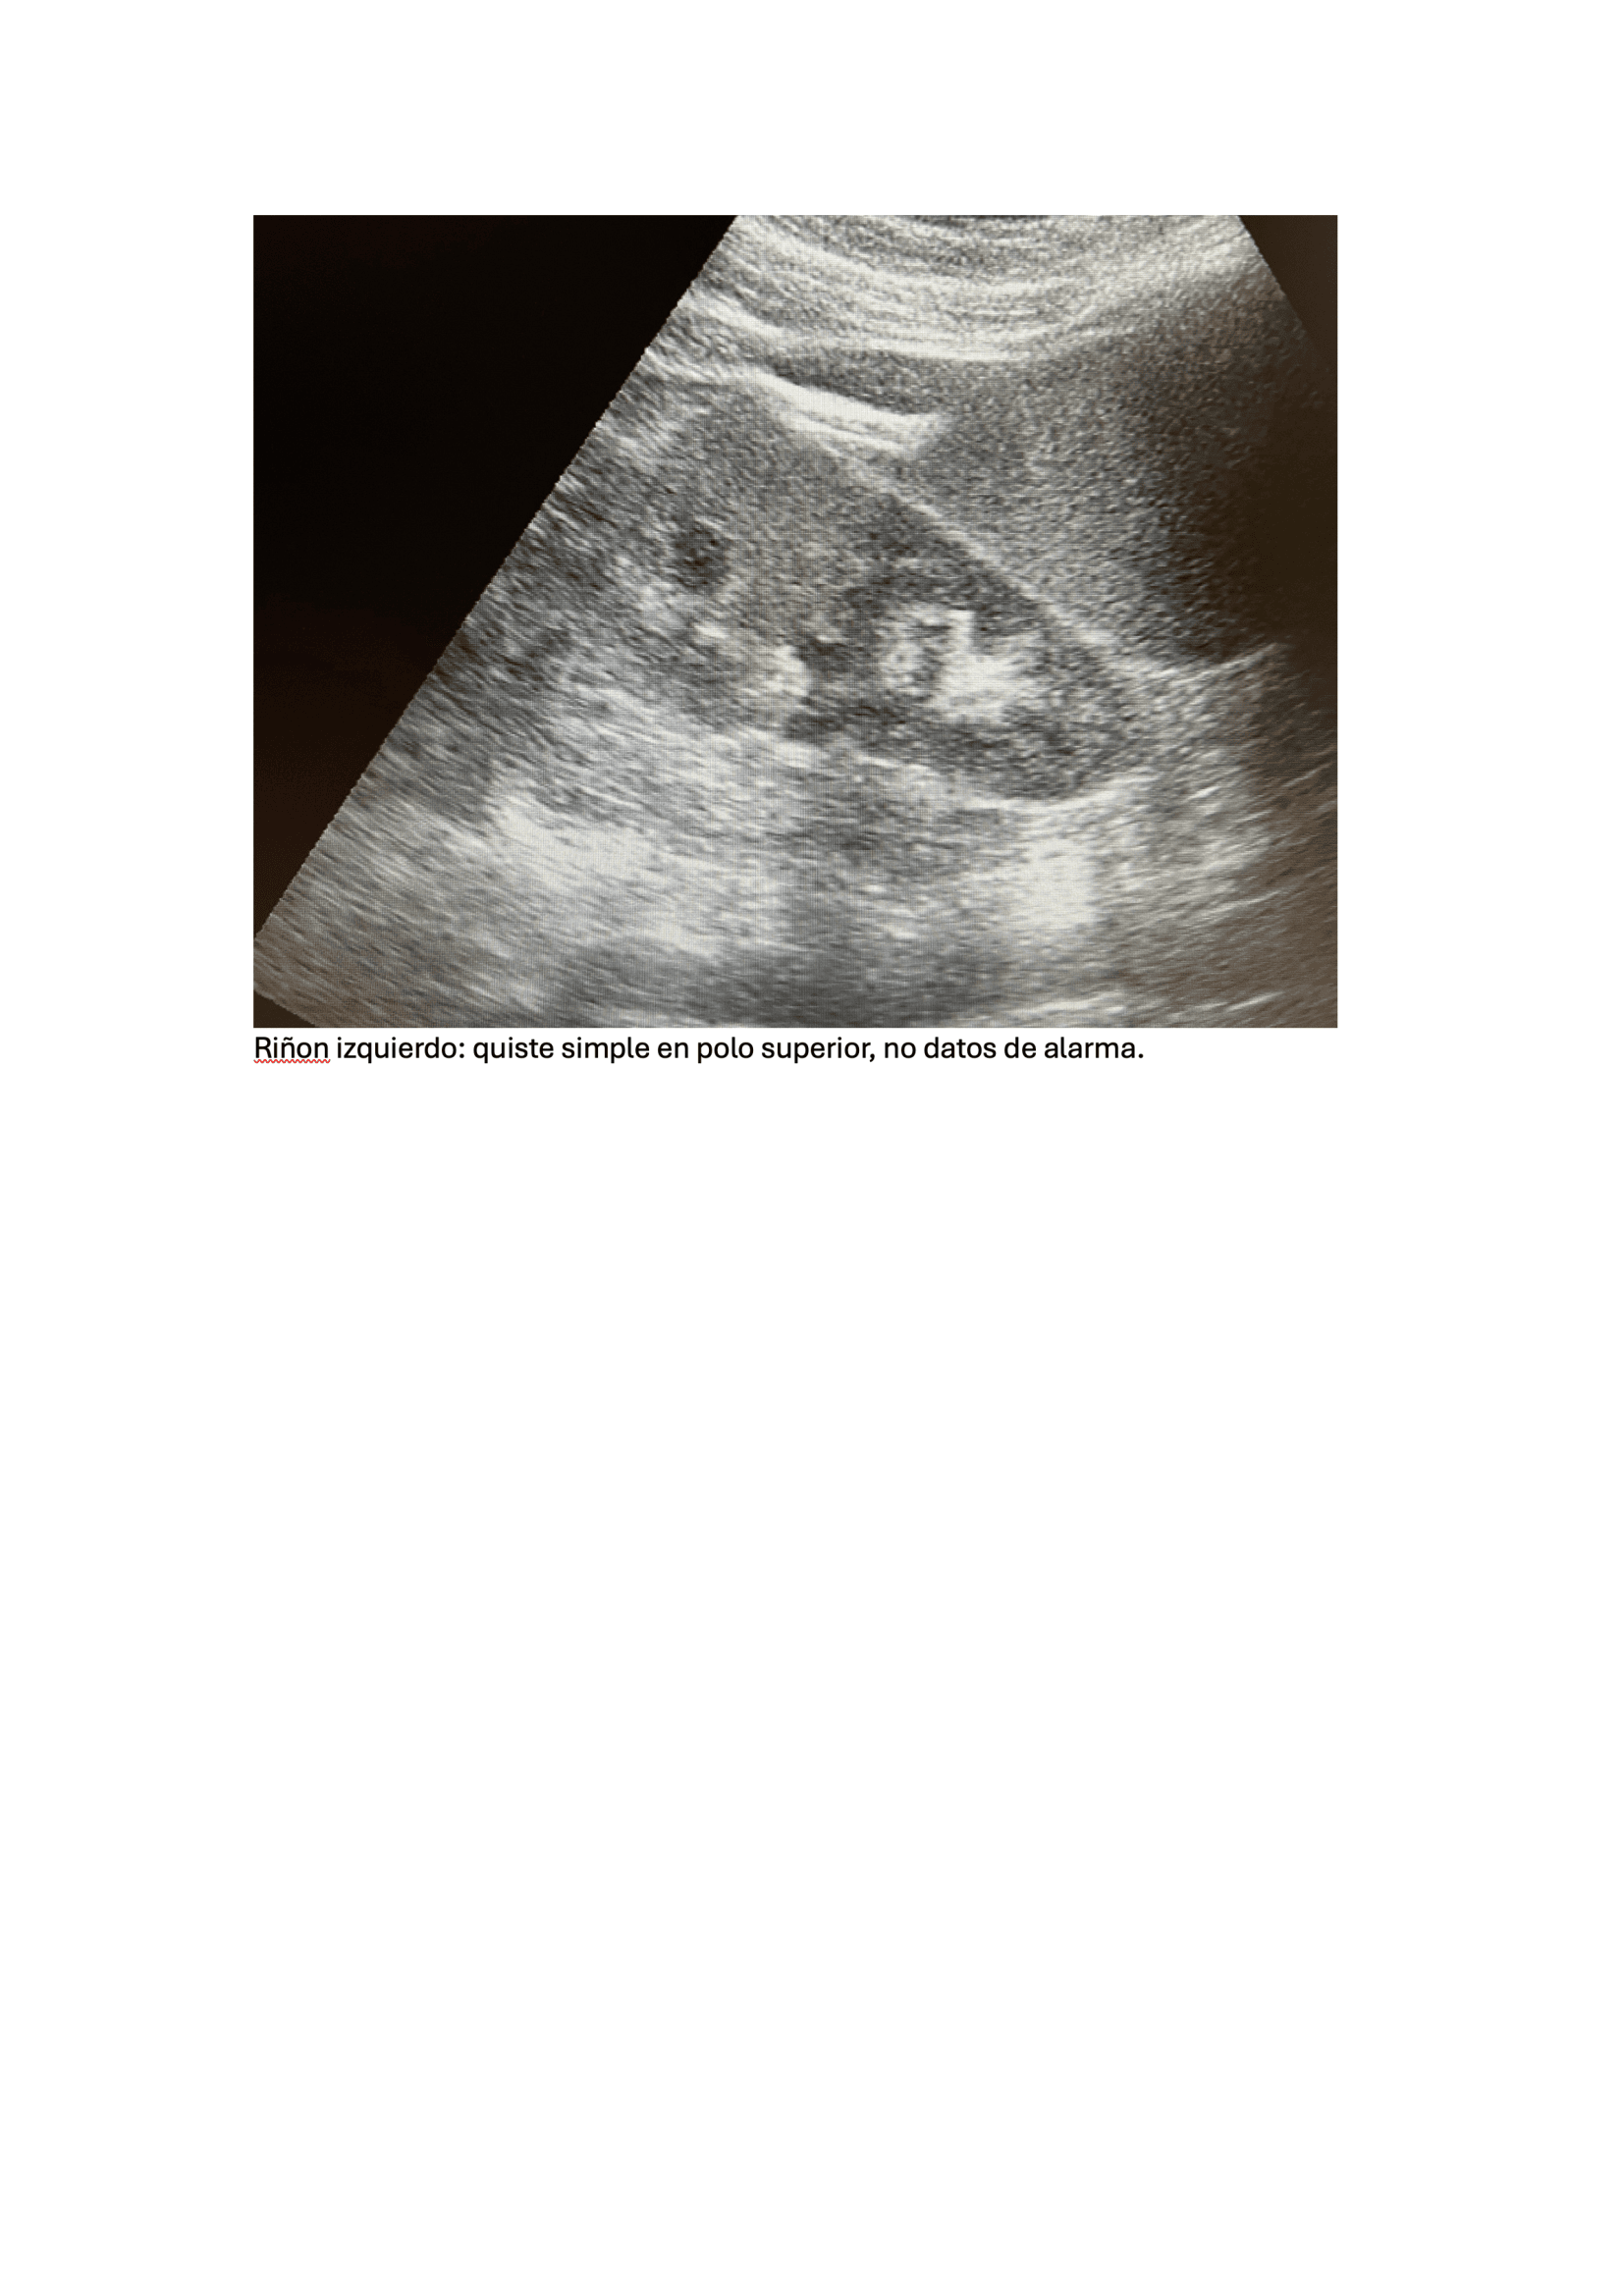

Exploración física, fiebre (39,5 °C) y taquicardia (FC: 120), puño-percusión positiva en la fosa lumbar derecha, sugiriendo una patología renal. Se realiza POCUS) que revela un riñón derecho aumentado de tamaño con una imagen lítica compatible con un cálculo renal de 1,2 cm x 8 mm, junto con dilatación de la pelvis renal (hidronefrosis grado I-II). Una tomografía computarizada (TAC) confirma los hallazgos y muestra un cálculo renal de 4 mm en la zona vesicoureteral distal, no obstruyendo totalmente la vía urinaria.

Urología: evidencia mejoría del cuadro clínico, niega fiebre, dolor. Refiere expulsión de pequeño cálculo tras 5 días de tratamiento. Ecografía, Riñón de tamaño normal, homogéneo, se evidencia imagen litiásica que deja sombra acústica posterior de 1,2 cm x 9 mm aprox. que no compromete vía urinaria, no dilatación de pelvis renal. Se deja tratamiento con tamsulosina durante 3 meses hasta nueva valoración. Control con su médico de familia, solicitar seguimiento de niveles ácido úrico y si alteración pautar tratamiento.